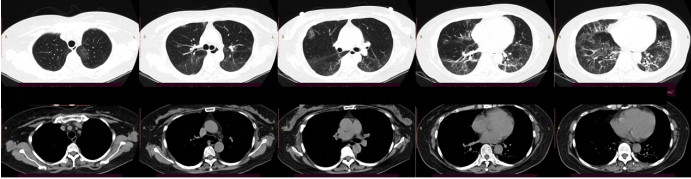

2022年5月底患者因着凉、劳累后出现咳嗽、咳痰,初始咳嗽不剧,伴少量痰,白痰,后咳嗽逐渐加重,伴活动后明显胸闷气促,夜间可平卧,有乏力、纳差,无发热、皮疹,无头痛、肌肉酸痛,无腹痛腹泻,无尿频、尿急、尿痛等。2022年6月5日就诊于当地医院,胸部CT示:两肺散在炎性病变,局部伴支气管扩张,双侧微量胸腔积液,双侧局部胸膜增厚。血常规:白细胞6.83×109/L、中性粒细胞百分比81.1%,CRP 77.24 mg/L,PCT 0.079 ng/mlESR 54 mm/h。血气分析(未吸氧):pH 7.45,PaO2 58.8 mmHg,PaCO2 33.4 mmHg,SaO90.7%。6月7日起出现发热,体温最高38.7℃,先后予莫西沙星、帕拉米韦及比阿培南抗感染治疗,仍有发热、咳嗽,活动后气促进行性加重。6月12日加用阿奇霉素+米诺环素抗感染治疗。6月13日复查胸部CT:两肺散在炎性病变伴间质性改变,局部伴支气管轻度扩张可能,较前进展,双侧少量胸腔积液,双侧局部胸膜增厚。6月14日复查血常规:WBC 4.91×109/L,NEU% 83.1%,CRP 96.74 mg/L,PCT 0.057 mg/ml,仍气促明显。6月15日至我院急诊就诊,胸部CT提示两肺散在炎性病变伴间质性改变,局部伴支气管轻度扩张可能,双侧少量胸腔积液,双侧局部胸膜增厚(图1)。查血常规:WBC 7.83×109/L,NEU% 83.2%,LYM% 11.5%。CRP 76.4 mg/L;PCT 0.05 ng/ml。动脉血气分析(面罩10 L/min):血浆pH 7.47,PaCO2 30.66 mmHg,PaO54.91 mmHg,SaO2 91.94%。考虑诊断:重症肺炎、Ⅰ型呼吸衰竭。予告病危,面罩吸氧,美罗培南抗感染,甲泼尼龙琥珀酸钠40 mg qd抗炎,茶碱、溴己新化痰平喘及抑酸护胃等对症治疗。现患者为求进一步诊治收入呼吸科监护室。患者自发病以来,神清,患者精神欠佳,纳差,二便无殊,体重无明显变化。

图片

1  患者胸部CT(2022年6月15日)

胸部CT:两肺见多发斑片状实变影伴磨玻璃影,局部小叶间隔增厚,内见支气管影,两肺下叶为著,两肺下叶支气管稍扩张,所见各支气管腔通畅,纵隔见稍大淋巴结,两侧胸膜稍增厚,两侧胸腔内少量积液。